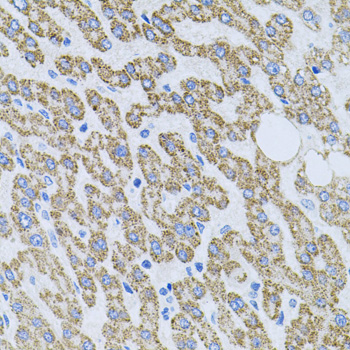

Immunohistochemistry of paraffin-embedded human liver damage using NTF4 antibody.